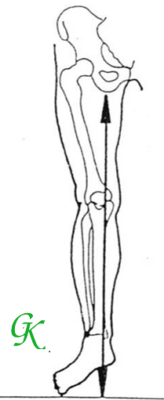

Hình 5. Nguyên lý kéo giảm, giảm tì đè trong thiết kế Nẹp chỉnh hình